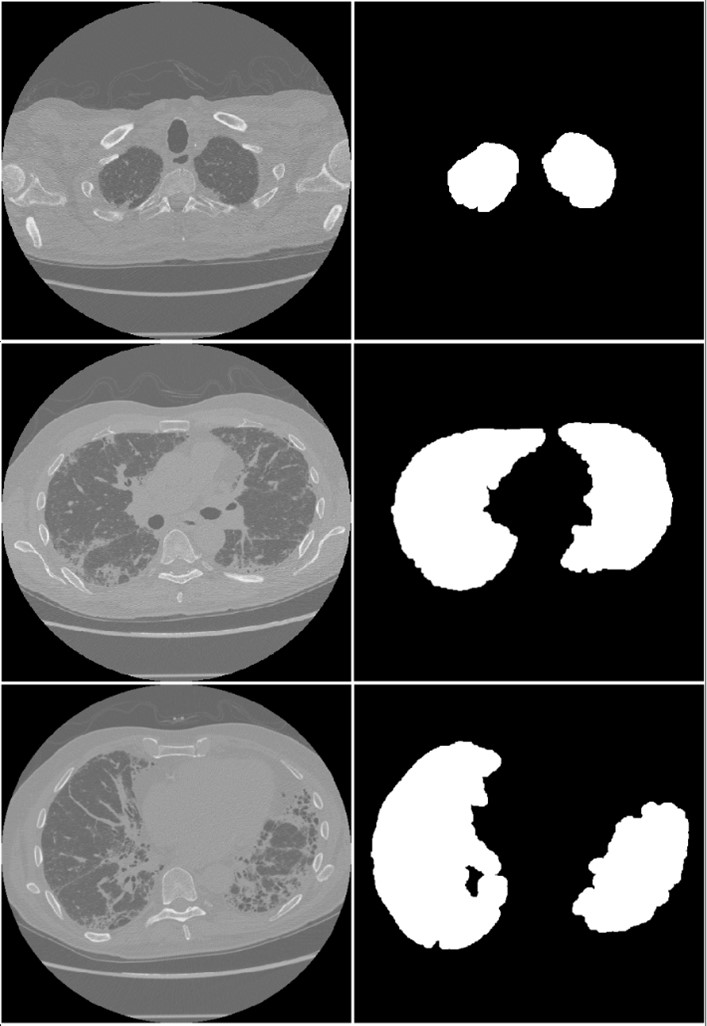

The mask corresponding to the lung region is first extracted from the input CT images using an automated method to make the context-aware model. We implemented an image processing workflow on the CT imaging dataset to automate the mask generation process and obviate the necessity for radiologist participation. This approach incorporated a region-growing algorithm (?), initiated by defining a seed point within the lung region, followed by morphological operations. Specifically, a dilation operator employing a circular structuring element was utilized after the region-growing segmentation. Examples of masks extracted using this method are shown in Figure 2.

Figure 2: Masks generated by the region growing algorithm for an upper lung slice (first row), middle slice (second row), and lower slice (third row) of the lung region.